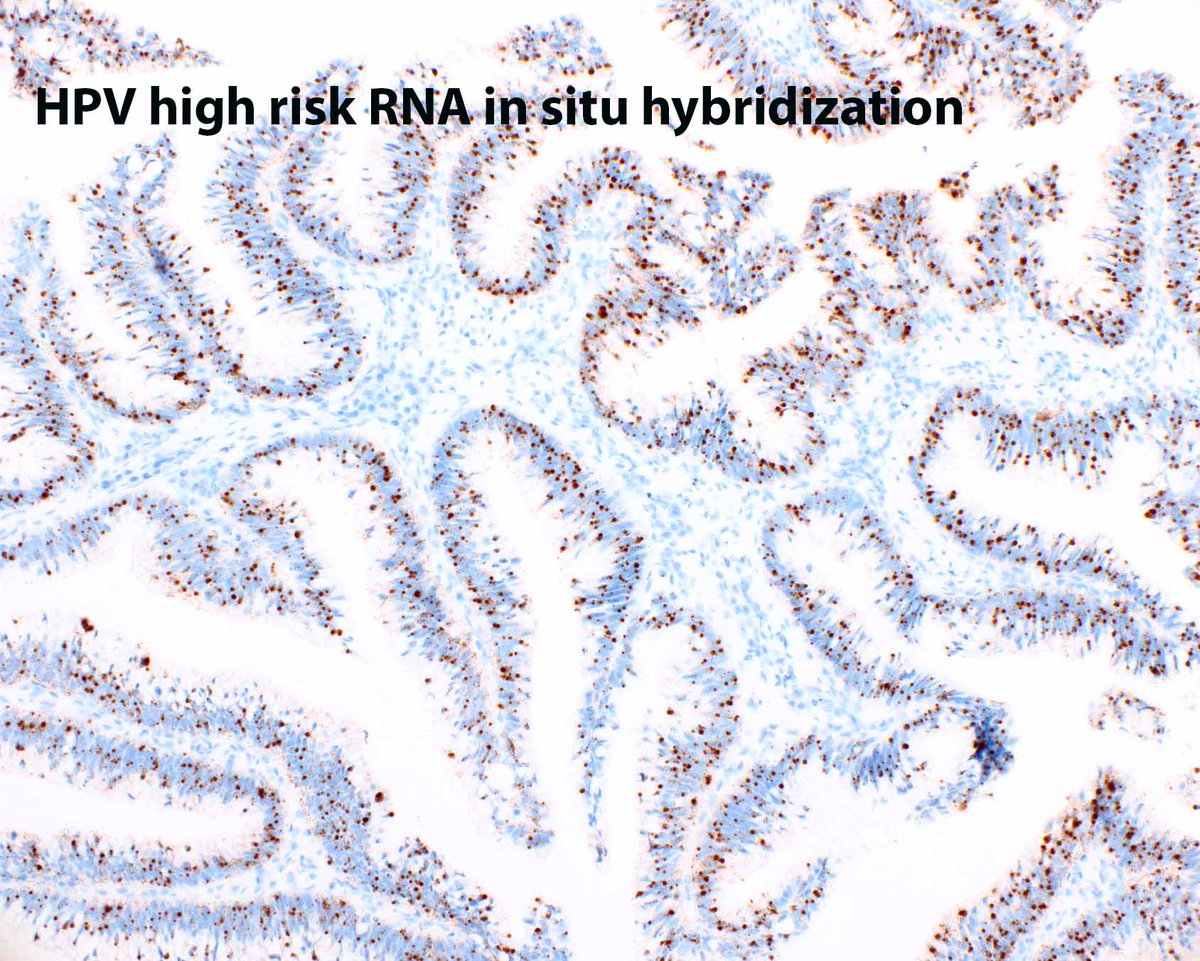

65 year old man posterior auricular neck deep dermal nodule. easy peezy?#dermpath #PathTwitter #dermatology Etan Marks, DO @ArjunRamaiya1 Lorand Kis Olaleke Folaranmi Tristan Rutland MBBS FRCPA IFCAP Trish Stratus Marcelasaeblima. Allison Osmond MD MSc FRCPC Ahmed Alomari, MD Gonzalo De Toro